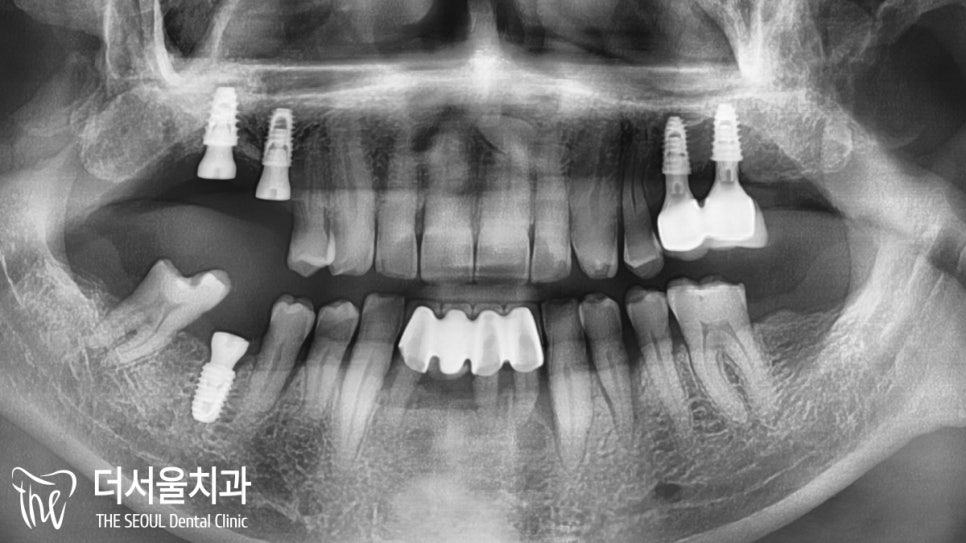

여러 차례의 골이식을 통해

픽스처를 심어드렸으며

안정적으로 고정이 되어있는 것을

확인할 수 있었습니다.

수차례의 골이식이 필요했지만

역시나 오늘도 별다른 문제 없이

식립을 마칠 수 있었네요.